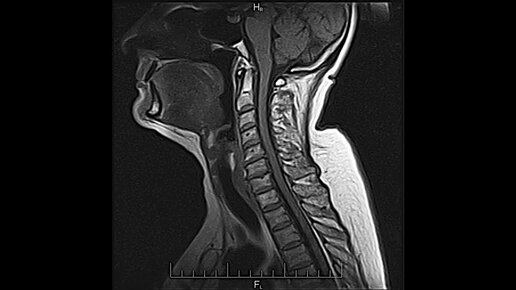

МРТ (магнитно-резонансная томография) горла и гортани – это неинвазивный метод визуализации, который использует мощное магнитное поле и радиоволны для получения подробных изображений мягких тканей, хрящей и других структур в области горла и гортани. В отличие от рентгена и КТ, МРТ не использует ионизирующее излучение. Что показывает МРТ горла и гортани: МРТ позволяет визуализировать и оценить следующие структуры и патологии: Гортань: Хрящи гортани (щитовидный, перстневидный, надгортанник и др.). Связки и мышцы гортани...